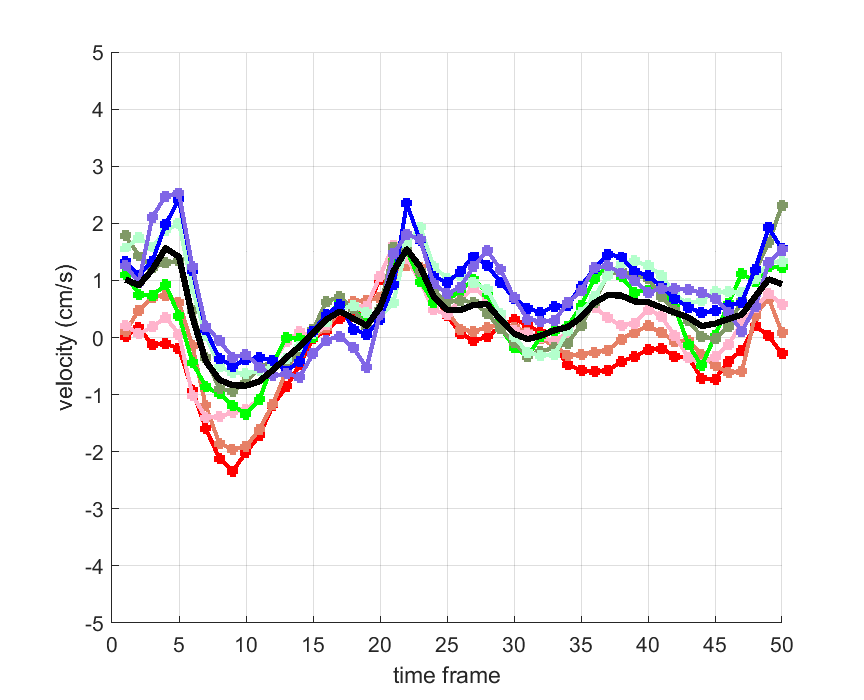

Time courses of the estimated translational component per subject, frame, slice and volume along the 3 velocity directions x, y and z are presented in Fig.6 - Fig.8.